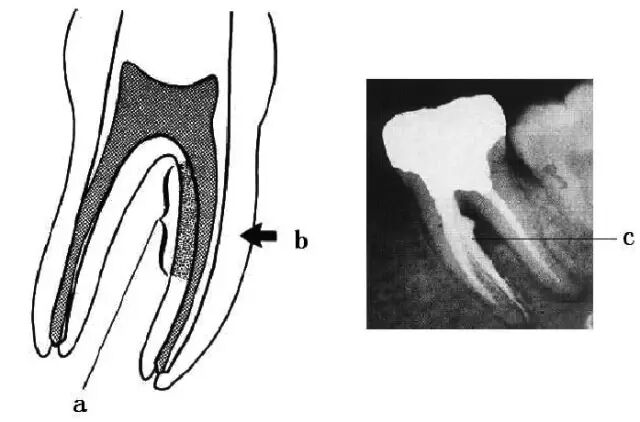

“G型扩孔钻预备:应用GG钻预备根管冠2/3可获得良好的根管冠部通道。GG钻进人根管前,一定要用10#或l5#根管锉探查和通畅根管,如果GG钻1#进入根管有困难时,应初步预备根管,再使用GG钻进入。一般来说,GGl#进入根管l6~17mm;GG2#,GG3#后退2~3mm;GG4#进入根管口下2~3mm;GG5#,GG6#仅作根管口以上部分预备,便于髓腔与根管口形成直线通道。GG钻勿进入根管的深部,避免过度去除牙本质,造成根管壁的薄弱,形成穿孔或瓶颈样预备(见下图)”

口腔H锉怎么消毒牙科医生必须看看----经典根管治疗总结_https://www.jmylbn.com_新闻资讯_第26张

图 根管带状侧穿(stripping,lateral wall perforation)

口腔H锉怎么消毒牙科医生必须看看----经典根管治疗总结_https://www.jmylbn.com_新闻资讯_第27张

图 根管的瓶颈样预备(右图)